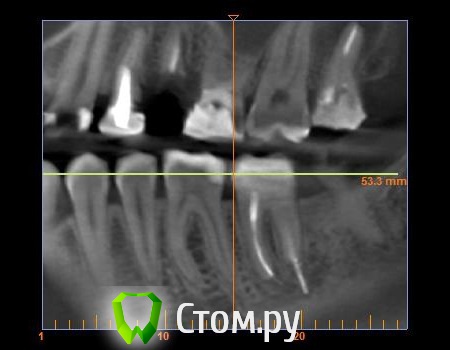

mastermind Опубликовано 22 августа, 2014 Автор Поделиться Опубликовано 22 августа, 2014 Нарезал 3 картинки из КТ Ссылка на комментарий